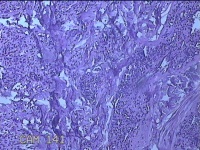

头皮结节

性别

男

年龄

33岁

临床诊断

皮肤赘生物

一般病史

发现头皮结节半个月余,无明显疼痛及不适。

标本名称

大体所见

灰白暗红色带皮肤样结节1x0.8x0.3cm一个,表面糜烂,切开结节呈实性,切面灰白粉红色,质软。

看不清,可能是毛细血管瘤,技术很需提高,不然迟早会。。。